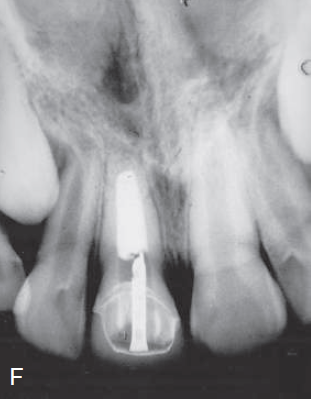

4 / 30

4. (Select ONE OR MORE correct answers)

The radiograph shows evidence of